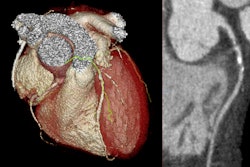

Coronary computed tomography angiography (CCTA) is a crucial diagnostic tool for chronic coronary syndrome and with advances in technology, it is now an important element of a radiologist’s expertise.